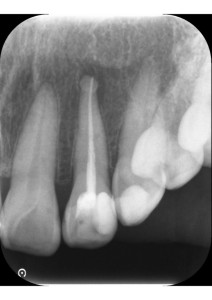

エックス線を撮影すると、右上奥歯2本、左下奥歯2本、左上前歯2本に虫歯が認められました。エックス線写真で診断するより実際は虫歯が深いことがあります。左下6番、左下7番、左上2番の計3本が神経に到達するほどの大きい虫歯でした。